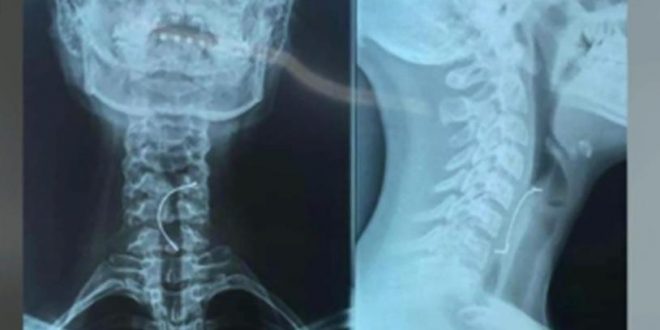

ESPECIAL.- Mientra comía en compañía de su familia, una adolescente se tragó accidentalmente una parte de sus brackets, lo cual causó que se perforara la garganta, dejándola en grave peligro.

Los padres llevaron a la menor de 15 años de edad a un hospital, donde los médicos le dijeron que el objeto le había perforado la garganta, por lo que de inmediato la intervinieron quirúrgicamente.

“Se atragantó con uno de los frenillos con un metal que liga los dientes, ella ingirió y quedó atascado a la mitad del esofago y eso produjo que tuviera muchos vomitos y no pudiera alimentarse” dijo el especialista.